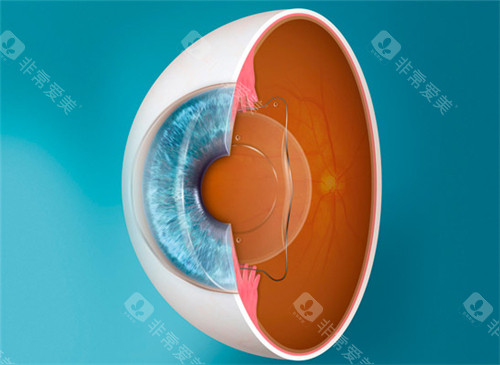

在眼科医疗领域,德国制造常被视为品质与技术的代名词。作为德国本土深耕眼科器械的品牌,德国人类光学(Human Optics)凭借其人工晶体产品,在白内障、老花眼等视力矫正领域占据重要地位。

其产品以“个性化适配+高性价比”为核心,覆盖单焦点、双焦点等类型,尤其适合高度近视、远视及复杂眼病患者。

3. 生物相容性优化,降低术后反应

临床数据显示,其单焦点晶体术后囊袋混浊率低于行业均值,这得益于其采用的亲水性丙烯酸酯材料。

该材料表面光滑,可减少蛋白质沉积,同时通过欧盟CE认证,确保长期使用的可靠性。

1. 定制化生产流程

从原材料筛选到成品出厂,每枚晶体需经历多道检测工序。例如,其亲水性材料需通过模拟人体环境的长期浸泡测试,确保生物相容性。